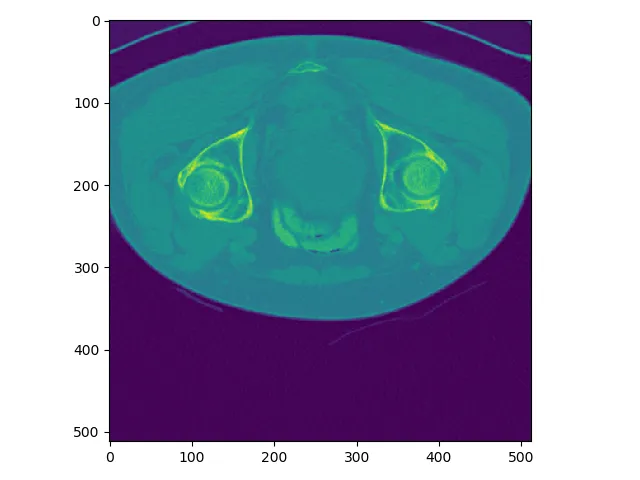

首先要明确一下和人体对应的方向,其中三个窗口对应三个切面,对应关系如下图所示,按照字母索引即可。例如,左上图对应R-A-L-P这个面,是从脚底往头部方向看的切面(即z方向),另外两张类似。

红色切面为矢状面,紫色切面为冠状面,绿色切面为横断面